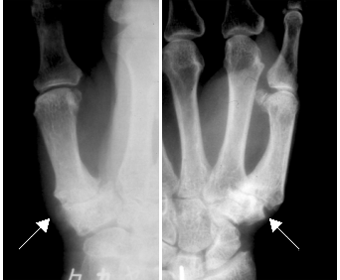

X線(レントゲン)検査でCM関節のすき間が狭く骨棘があったり、ときには亜脱臼が認められます。